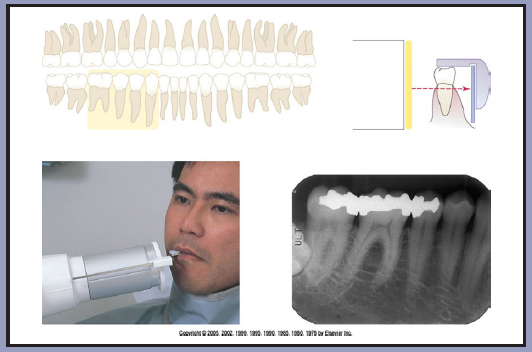

Bitewing images are parallel images because the receptor is positioned parallel to the long axis of the teeth and the beam is perpendicular to the receptor as in Figure 60. A bitewing tab is utilized to stabilize the receptor as the patient bites together.

Beam Angulation and Receptor Holding Devices

Bitewing radiographic images are usually exposed with an indicated vertical angulation of +10 degrees (tube head points down for positive (+) angulation). This angulation provides an acceptable compromise for the differences between the long axis inclinations of the maxillary and mandibular teeth. Horizontal angulation is aligned with the direction of the contact, and the central ray is directed between the contacts of the teeth to be radiographed. Horizontal angulation is achieved when the central ray of the x-ray beam is directed specifically between the contacts of the teeth to be radiographed.

The interproximal examination may be done using a special type 3 bitewing receptor but is preferably achieved by using type 2 receptors fitted with a tab. (Figure 61) There are also receptor holding devices available that support the receptor as well as provide an external reference for positioning the tube head. The patient stabilizes the receptor by gently biting together on the manufactured tab or on the holding device.

Tube head position is illustrated in Figure 62, and a sample set of bitewing radiographic images are illustrated in Figure 63.

Figure 60 – Bitewing placement

Figure 60

Figure 61 – Bitewing Tab on Type 2 Receptor

Figure 61

Figure 62 – Bitewing Placement

Figure 62